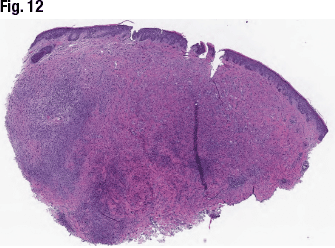

[dropcap]T[/dropcap]he next case is that of a 64-year-old male with a lesion on his right forehead. In Fig. 12 is the diffuse melanocytic lesion with hypo- and hypercellular area. Three cytomorphology features (epithelioid, nevoid, and balloon cells) are seen on high power (Fig. 13). “And the lesions also show associated lymphoid aggregates—one of the features of this type of lesion,” Dr. Aung said. Some of the epithelioid cells show cytologic atypia. “However, buffer MART-1/Ki67 showed low or absent proliferative index,” she said (Fig. 14). The dermal melanocytes showed loss of BAP1 nuclear expression (Fig. 15, compared with positive control showing nuclear BAP1 expression in the keratinocytes within epidermis [inset]). “And BRAF V600E immunohistochemical studies showed positive staining pattern, indicating mutation in these melanocytes” (Fig. 16).